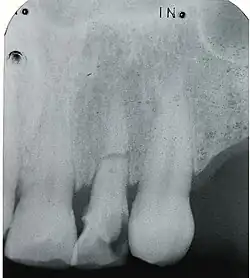

Kronenfraktur mit gut erkennbarer Pulpaeröffnung an Zahn 11. 16-jähriger Patient, -

Röntgenbild (Zahnfilm) des frakturierten Zahnes -